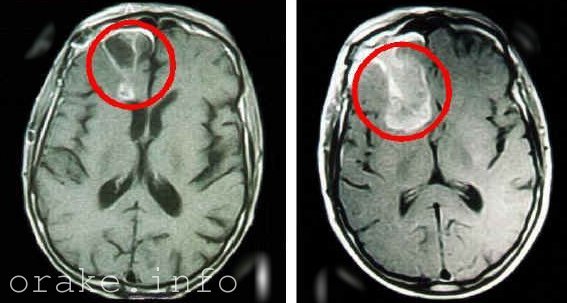

Рак головного мозга у детей – это злокачественная опухоль, которая развивается из клеток мозговой ткани. Ему характерно инфильтрационный рост (врастание патологически измененных клеток в близлежащие ткани органа) и образование метастазов (распространение мутированных клеток по всему организму через лимфатические и кровеносные сосуды).

Опухоли головного мозга у детей

Существует два наиболее распространенных типа опухоли головного мозга у детей: